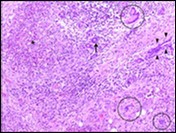

Figure 2.Granulomatous mastitis with articulated epitheloid cell granuloma, lymphocytic, plasma cell and neutrophilic infiltration10.

Core needle biopsy of idiopathic granulomatous mastitis enunciates multiple aggregates of non- caseating epitheloid cell granulomas within and encompassing breast lobules, constituted of epitheloid histiocytes, lymphocytes, neutrophils and multinucleated giant cells. Granulomatous inflammation is predominantly lobulo-centric. The inflammation is preponderantly composed of lymphocytes, plasma cells, epitheloid histiocytes, multinucleated giant cells and neutrophils. Neutrophils can configure micro-abscesses and encompass vacant micro-cystic cavities, morphological features which are in common with cystic neutrophilic granulomatous mastitis. Non specific lobulitis along with a lymphoid and plasma cell infiltrate accompanies the granulomatous inflammation. Necrosis is usually absent. Neutrophilic micro-abscesses can be accompanied by fistula formation 4, 5.

Multinucleated giant cells are detected in an estimated three fourths (78.5%) instances. Plasma cells are discernible in around half (53.9%) of the subjects and usually appear at the margins of cystic vacuoles with centric accumulation of neutrophils within the granulomas.